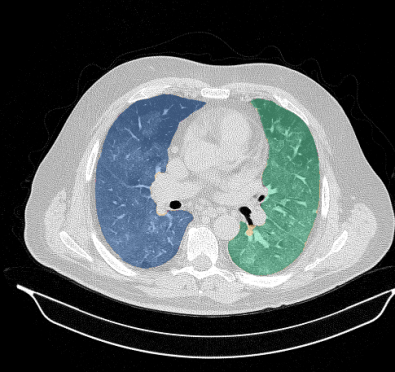

Lung segmentation results for the polymorphic and nonpolymorphic models are shown in Figure 3. Quantitative evaluation of lung segmentations was performed on CT images by comparing the segmentations to ground truth manual segmentations. The Dice coefficient was used to measure volume overlap and the average symmetric surface distance (ASSD) was used to assess boundary accuracy. The ASSD and Dice coefficient results for each of the four evaluation datasets are shown in Table 2. Overall, on the COVID-19 dataset the polymorphic model achieved an average ASSD of mm and average Dice coefficient of . By comparison, the nonpolymorphic model achieved an average ASSD of mm and average Dice coefficient of . ASSD and Dice coefficient results with respect to nonaerated lung volume fraction are displayed in Figure 4. Two-way analysis of variance revealed a significant interaction between model and nonaerated fraction for each evaluation metric, indicating that the regression coefficients with respect to nonaerated fraction were significantly different for polymorphic vs. nonpolymorphic models.